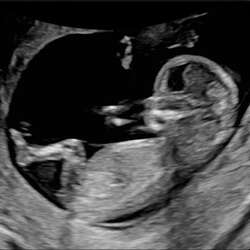

Jaa herken ik heel erg. Het is dat ik het op de echo zie en het hartje hoor maar is het zo onwerkelijk. Ook wel omdat ik echt 0 symptomen heb (gehad)

Ontopic; hier is het ook herkenbaar. Ik voel de kleine nog niet en zelfs met echo's vind ik het net lijken alsof ze een filmpje afspelen... voelt ook nog heel gek om spullen te kopen e.d. daardoor.

Heel fijn om te lezen dat ik dus niet de enige ben! Ik ben vandaag 16 weken en het voelt nog zo onwerkelijk. Op sommige dagen 'vergeet' ik bijna dat ik zwanger ben. De aankondiging versturen via de app heb ik ook wekenlang uitgesteld, het voelde zo raar om het te delen. Alsof het niet over mij gaat. Tijdens de echo's is er even een besef momentje, maar dat is ook snel weer verdwenen.